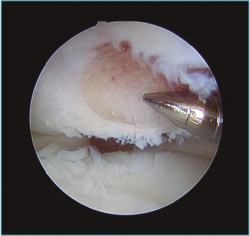

Los portales más adecuados son el anteromedial proximal para la óptica y el anterolateral, el anterolateral proximal y el mediolateral directo o soft-spot (Figura 4) como portales de trabajo. Los portales anteromediales permiten una excelente visualización de la cámara anterior, de la superficie articular de la cabeza radial, del cóndilo humeral, de la apófisis coronoides y de la cápsula anterior y lateral (Figura 5). A este nivel suelen observarse la gran mayoría de los cuerpos libres articulares que en ocasiones se encuentran en la zona lateral y posterior del codo (Figura 6).

Figura 5. Imagen artroscópica de defecto condral en porción anteroinferior de capitellum. Óptica en portal anteromedial proximal.

Figura 8. Desbridamiento de una lesión osteocondral en la porción inferior del capitellum y perforaciones. Visión desde portal mediolateral directo.